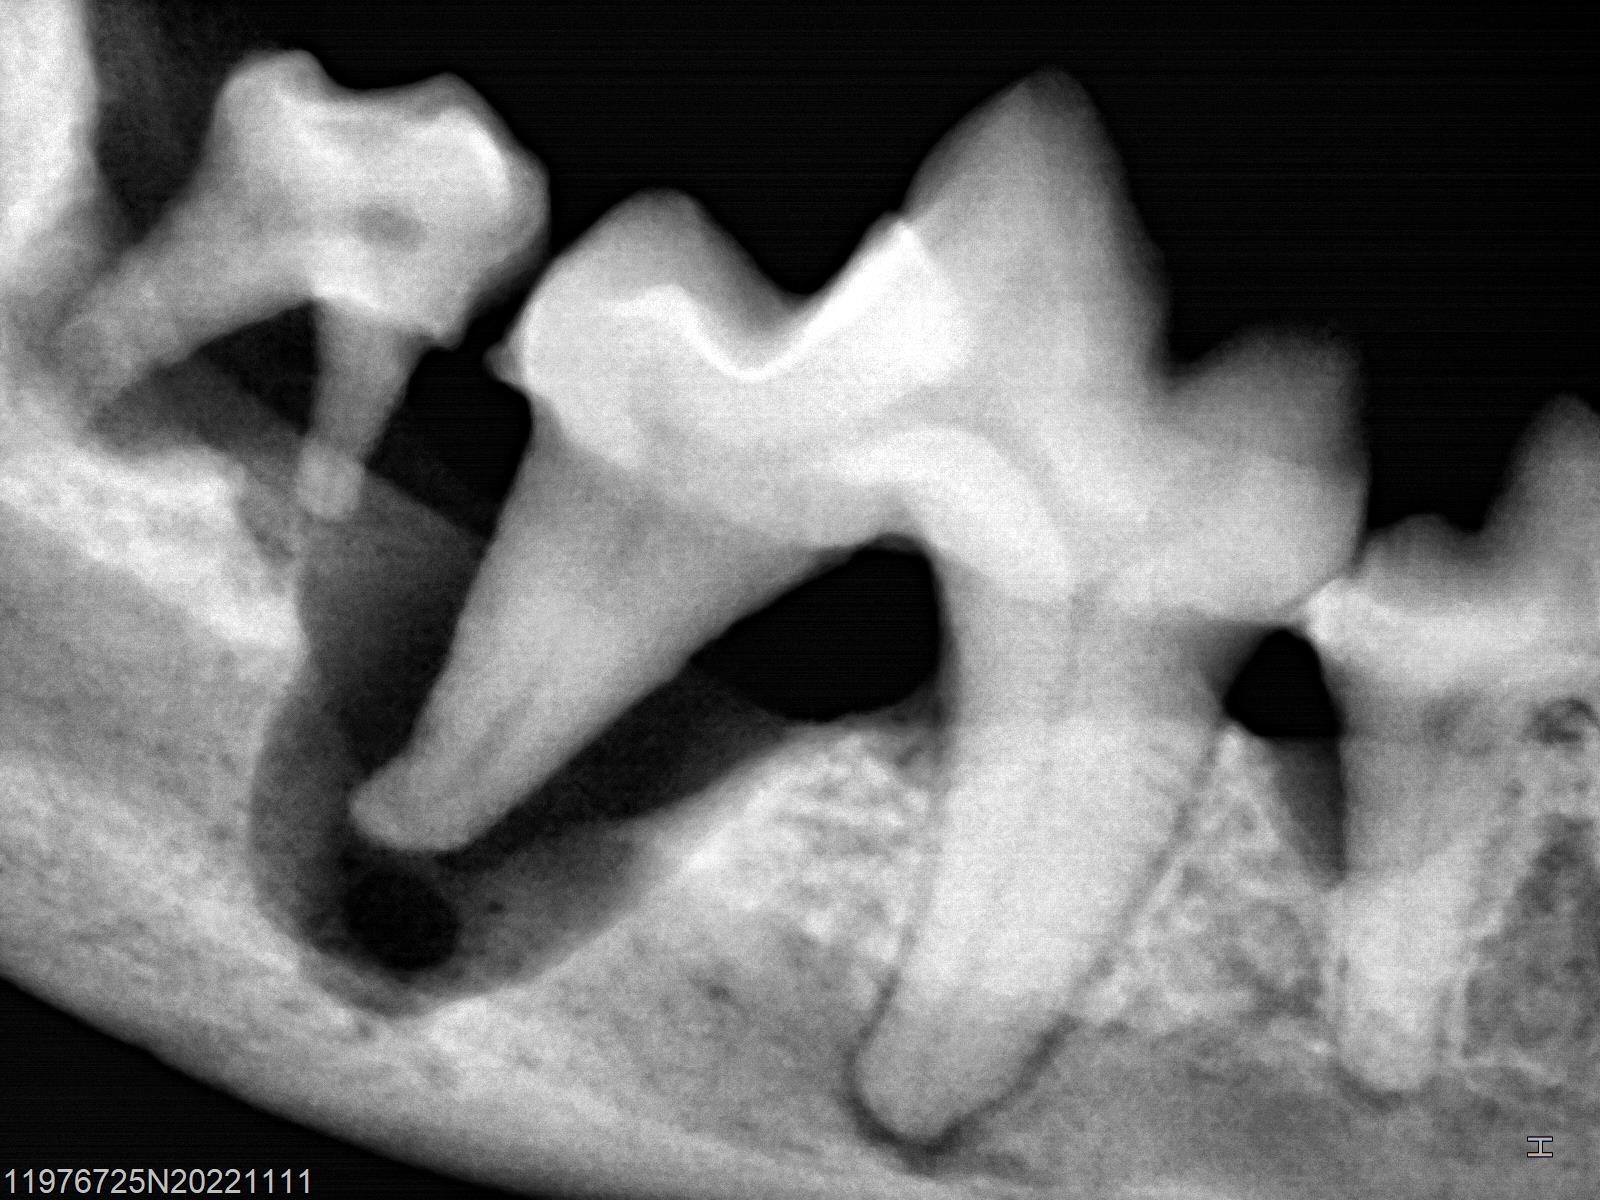

歯科X線検査

麻酔下における歯科処置は比較的件数の多い手術です。

歯石除去やスケーリングで歯の健康を整えたり、

場合によっては歯周病の進行により

抜歯が必要になるケースもあります。

数ヶ月前より歯科X線機器を当院で導入しました。

この検査機器を用いることで、通常のX線検査ではわかりにくい

歯周病の進行具合がよくわかります。

この子の歯は見た目、歯肉も後退してなくて

歯を温存できそうに見えますが・・

歯周病の犬歯科X線撮影をしてみると、

歯周病で下顎が溶けているレントゲン画像このように歯の根元の周りの骨が溶けていることが分かります。

この歯を残しておくと結局匂いの元になったり、

歯周病の進行につながり、最悪、顎の骨が折れてしまうこともあります。

この歯は抜歯をしなければなりません。